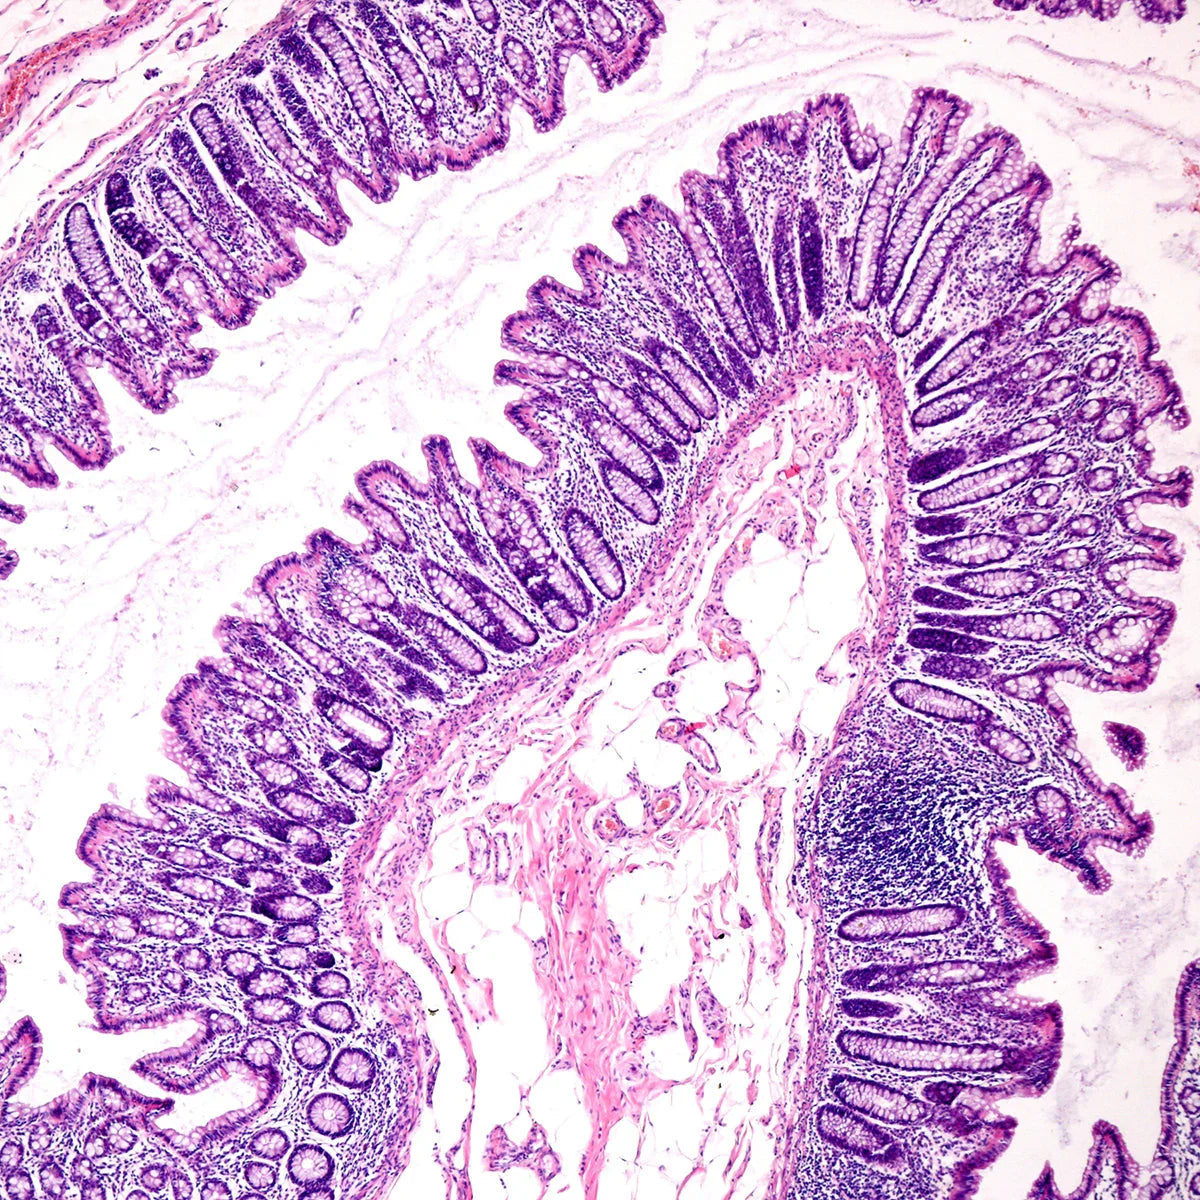

Läckande tarm-syndrom är ofta förknippat med en obalans i tarmfloran. En minskning av gynnsamma bakterier och en ökning av skadliga bakterier kan bidra till en ökad tarmpermeabilitet. Tillskott av probiotika hjälper till att återställa balansen i tarmfloran, vilket är avgörande för att upprätthålla tarmhälsa och korrekt funktion.

Läckande tarm-syndrom åtföljs nästan alltid av kronisk inflammation, eftersom ämnen som läcker från tarmen ut i blodomloppet utlöser immunsvar. Probiotika kan hjälpa till att minska denna inflammatoriska respons genom att modulera immunfunktionen och stödja antiinflammatoriska processer. Detta är särskilt viktigt för läkning av tarmväggen och minskning av övergripande inflammatoriska tillstånd.